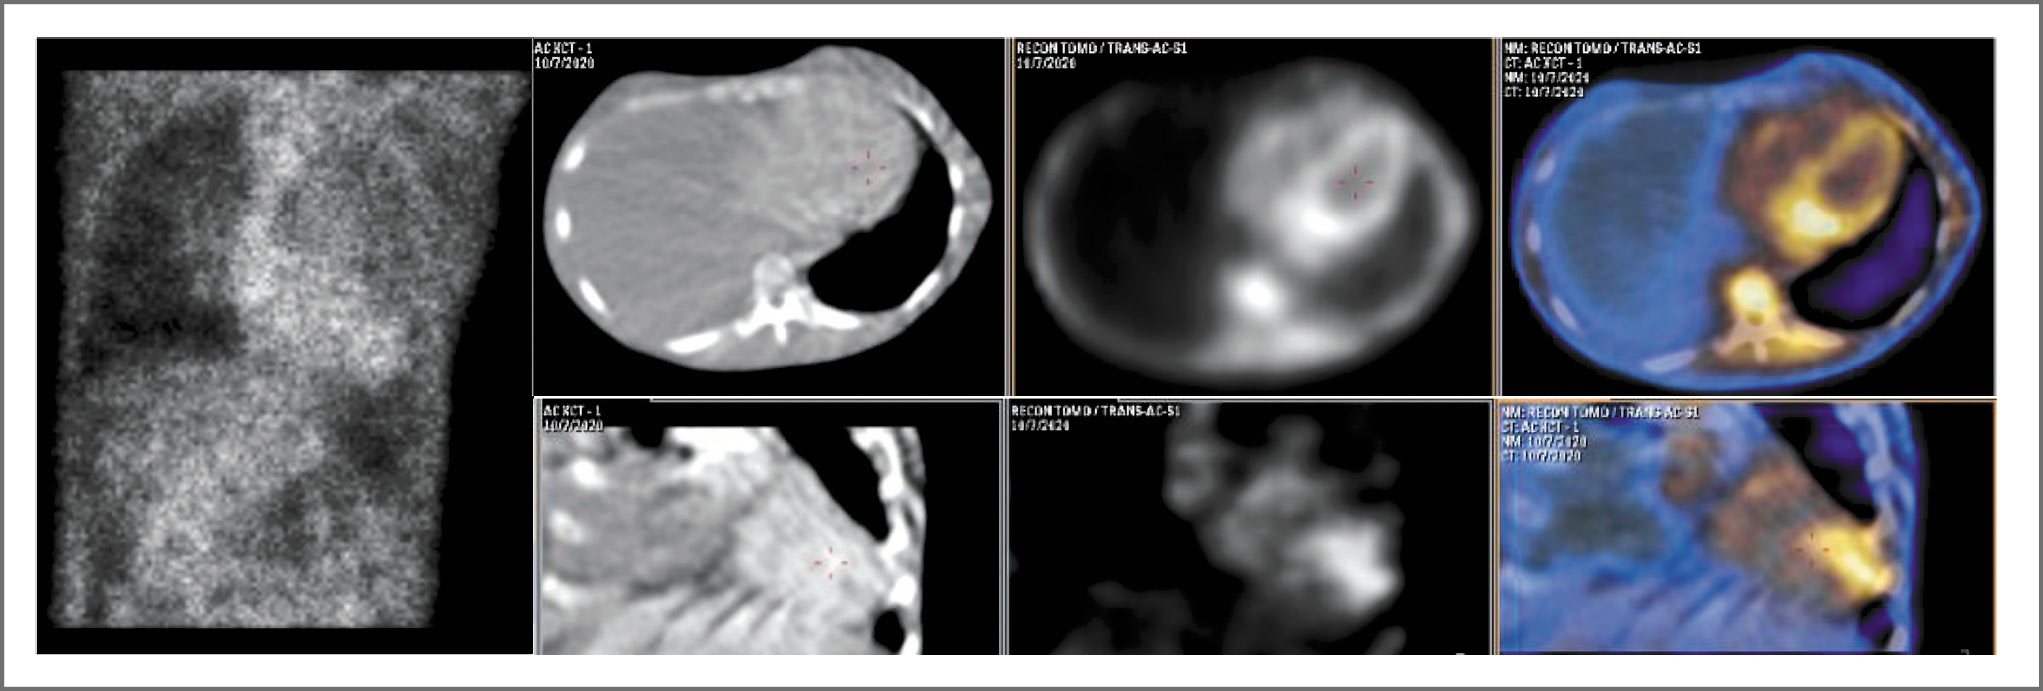

После гистологического подтверждения амилоидоза необходимо его типирование для выбора правильного метода лечения, который определяет специфическую терапию амилоидоза. Типирование может быть осуществлено путем дополнительного исследования гистологического материала, например при помощи иммуногистохимического исследования с использованием антител к белкам- предшественникам амилоида или путем направления материала с гистологически подтвержденным амилоидом на масс-спектрометрический анализ. Однако существует и малоинвазивный инструментальный алгоритм типирования – сцинтиграфия миокарда с 99mTc-пирофосфатом – более доступный для крупных кардиологических центров и позволяющий верифицировать ATTR-вариант. При оценке результатов сцинтиграфии миокарда с 99mTc-пирофосфатом в режиме однофотонной эмиссионной компьютерной томографии – ОЭКТ (рис. 4) картина не позволяла исключить ATTR-амилоидоз, поскольку визуализируется интенсивное накопление радиофармпрепарата (РФП) во всем миокарде ЛЖ с очагами повышенного включения в апикальных и нижних сегментах, соотношение накопления РФП в миокарде и в контрлатеральной зоне 2,36 (grade 2–3); очаговое накопление РФП в проекции фиброзного клапанного кольца (признак активного воспалительного процесса); минимальное накопление РФП в пуле крови (признак застойных явлений по большому кругу кровообращения).

Рис. 4. Данные планарной сцинтиграфии, КТ, ОЭКТ и ОЭКТ/КТ пациента с верифицированным AL-амилоидозом. Визуализируется интенсивное накопление РФП во всем миокарде ЛЖ с очагами повышенного включения в апикальных и нижних сегментах (Grade 2–3).

Fig. 4. Data of planar scintigraphy, CT, SPECT and SPECT/CT scan of a patient with verified AL-amyloidosis. Intensive accumulation of radio pharma drug in the entire myocardium of the left ventricle with centers of increased inclusion in the apical and lower segments is visualized (Grade 2–3).

В итоге, несмотря на первоначально полученные отрицательные результаты иммунофиксации сыворотки крови и сомнительные данные остеотропной сцинтиграфии миокарда, установлен следующий диагноз – «системный AL-амилоидоз с преимущественным поражением сердца, поражением желудочно-кишечного тракта, нервной системы, кожи, почек. Хроническая СН IIБ стадии, III функционального класса по NYHA». При ретроспективном анализе полученные данные сцинтиграфии миокарда расценены как проявление диффузного некроза миокарда, наиболее выраженного в апикальном сегменте ЛЖ и свидетельствующего о наступлении терминальной стадии основного заболевания. К сожалению, пациентке не проводился анализ крови на тропонин, однако в мировой литературе имеется публикация с описанием подобного случая течения AL-амилоидоза в терминальной фазе с уровнем тропонина Т 273,4 нг/мл (N 0–14), NT-ProBNP 23 000 пг/мл (N 0–88), ФВ ЛЖ 23%, значением HCl 1,65 и Grade 2 у пациента, скончавшегося через 2 мес после выписки [12].